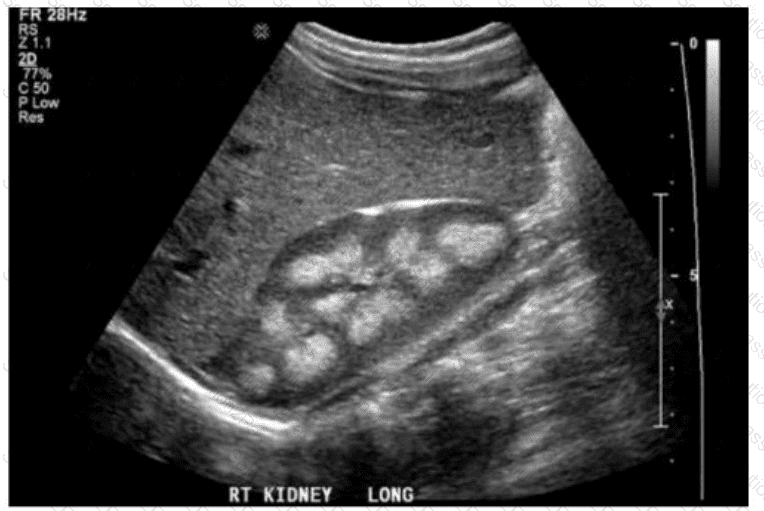

Which diagnosis is most accurate based on the findings in this image from an adult patient?